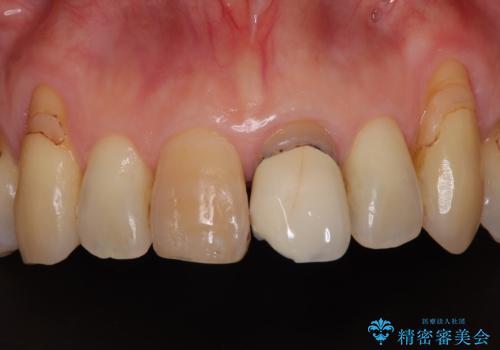

しみる前歯のセラミック治療 周辺も同時に治療して調和の取れた前歯に